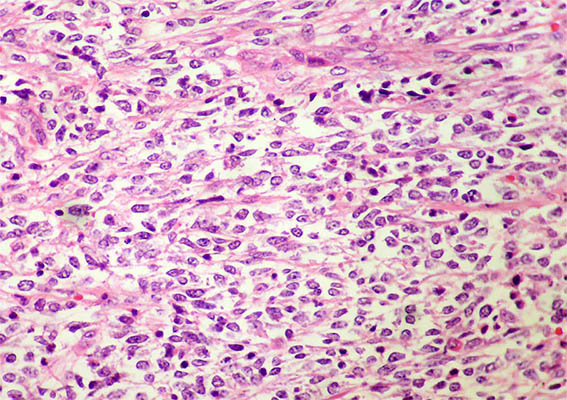

Figure 6. H&E, X400.

Figure 7. H&E, X400.

Myogenin, CD99, CD45, S100, chromogranin, synaptophysin, cytokeratins: Negative. INI1: diffuse nuclear positivity.